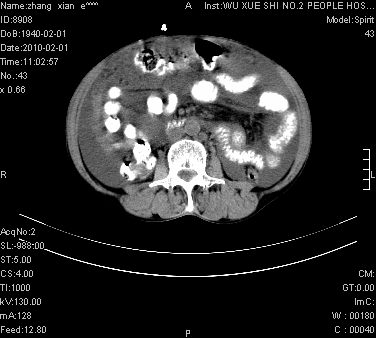

标题: CT24434:70岁 女 腹胀,腹水原因待查 [打印本页]

大量腹水,脾脏囊性占位,子宫颈占位,右侧腹股沟淋巴结肿大,建议+c,先查妇科。

腹盆腔大量积液,子宫增大,子宫颈增大外形不规则,内见低密度影,膀胱后壁显示不清,右腹股沟肿大淋巴结,脾脏囊性占位,子宫颈占位,子宫颈癌?建议增强。

考虑:1、腹膜转移,大量腹水;

2、脾占位性病变;

3、左侧卵巢占位性病变,建议增强进一步检查。